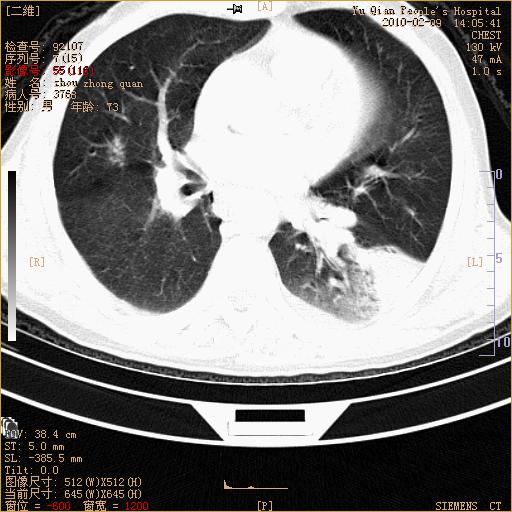

男性,73岁,咳嗽咳血数天,诊为肺ca伴左肺下叶后段阻塞性炎症、肺不张妥否?

右下肺有转移?

左下肺中央型肺癌伴结段形肺不张,左侧胸腔积液,纵隔内见部分增大淋巴结(反应性增生或转移)

左下基底干支气管明显变窄。

左肺下叶基底段支气管狭窄,左肺门增大,左肺下叶团片状病灶。中心型肺癌伴柱塞性炎症可能大,建议支气管镜检查。

左下肺中央型肺癌伴节段性肺不张,左侧胸腔积液,纵隔内见肿大淋巴结

左下基底段支气管变窄。建议进一步纤支镜检查。

1、左肺下叶后基地段肺癌伴阻塞性炎症,左下肺门淋巴结转移。2、左侧胸腔积液。